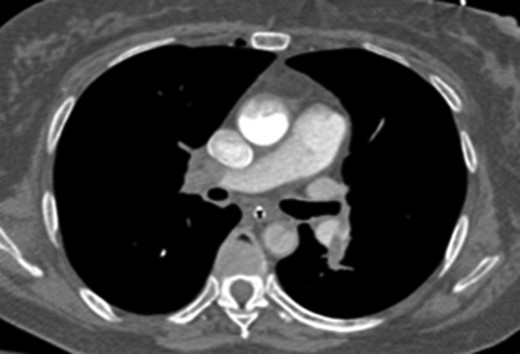

Once stable, imaging confirmed PE (Fig. 2) with a RV to left ventricle (LV) ratio of 2.1 (Fig. 3). The patient was then admitted to the ICU requiring inotropic support. Approximately 4 h later, the patient had concerning features of abdominal compartmental syndrome with increase abdominal distention and bladder pressures >25 mmHg was noted. Repeat imaging showed large volume hemoperitoneum emanating from the left hepatic lobe (Fig. 4). The patient underwent a decompressive laparotomy with a non-anatomic liver resection of segments I and II and temporary abdominal closure. Due to concerns of distal limb ischemia of the arterial cannulation site, an 8-Fr reperfusion cannula was placed in the left superficial femoral artery (SFA).

CTA chest showing significant pulmonary embolic clot burden occluding the right and left upper lung lobes.